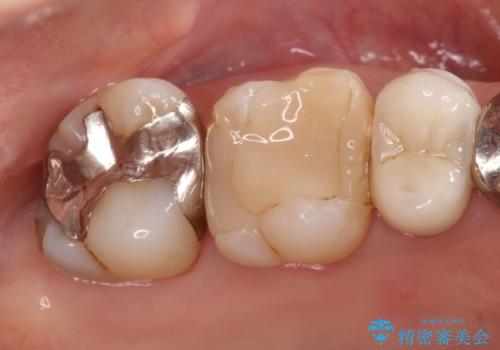

- 定期検診にて虫歯を見つけ、メタルボンドクラウンにて修復補綴治療を行なっております。

歯肉縁下まで虫歯が進行していたため歯周外科を併用して治療を行なっております。

メタルボンドクラウンは内側に金属のフレーム、外側にセラミックを使用した被せ物です。